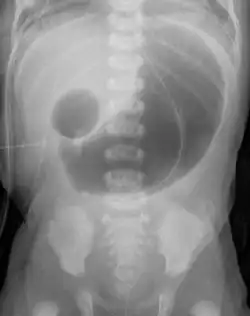

Radiograph with double bubble sign indicating duodenal atresia

If not diagnosed in utero, infants with intestinal atresia are typically diagnosed at day 1 or day 2 after presenting with eating problems, vomiting, and/or failure to have a bowel movement.[3] Diagnosis can be confirmed with an X-ray, and typically followed with an upper gastrointestinal series, lower gastrointestinal series, and ultrasound.[5][3]